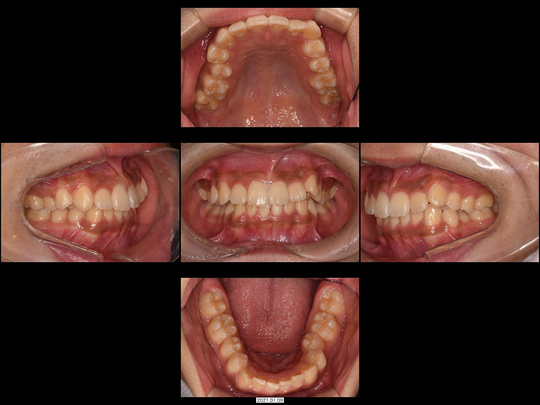

Mさん 20代 男性

矯正前

画像をクリックで拡大

矯正後

治療の説明

マウスピース型矯正装置を使った矯正治療にて、下あごのみ治療しました。歯は抜いておりません。

治療の期間・回数

10か月、8回

​費用

563,200円